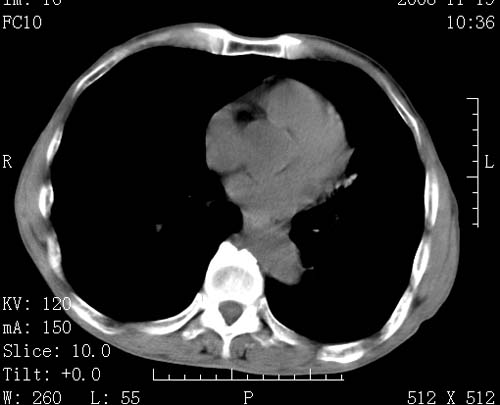

标题: CT16691:m 67 胃镜确诊食管下段及贲门癌 [打印本页]

标题: CT16691:m 67 胃镜确诊食管下段及贲门癌

术前查体,双肺部结节是转移?结核?请点评

1)符合食管癌表现。2)两肺及纵隔淋巴结多发性转移瘤。3)左肺上叶舌段及两肺下叶炎症感染。

食管癌伴双肺转移,评述:肺部毛细血管网丰富,全身血液均快速流经肺部,癌细胞容易过滤定植,形成转移瘤,影象特点为以毛细血管末梢为中心的结节灶,边缘光滑锐利,少见有中心空洞着,不同来源的转移瘤可有各自特点,如甲状腺癌为双肺弥漫性微结节,本例有原发灶,双肺影象灶典型,左肺舌段条带状网格样伴胸膜天幕征,可视为癌性淋巴管炎。

符合食管癌表现。两肺及纵隔淋巴结多发性转移瘤。双肺还有支扩表现.

左肺舌段有斑点钙化灶,能否说明是结核而不是转移?如果是转移将放弃手术改成化疗,如果是结核将考虑择期手术